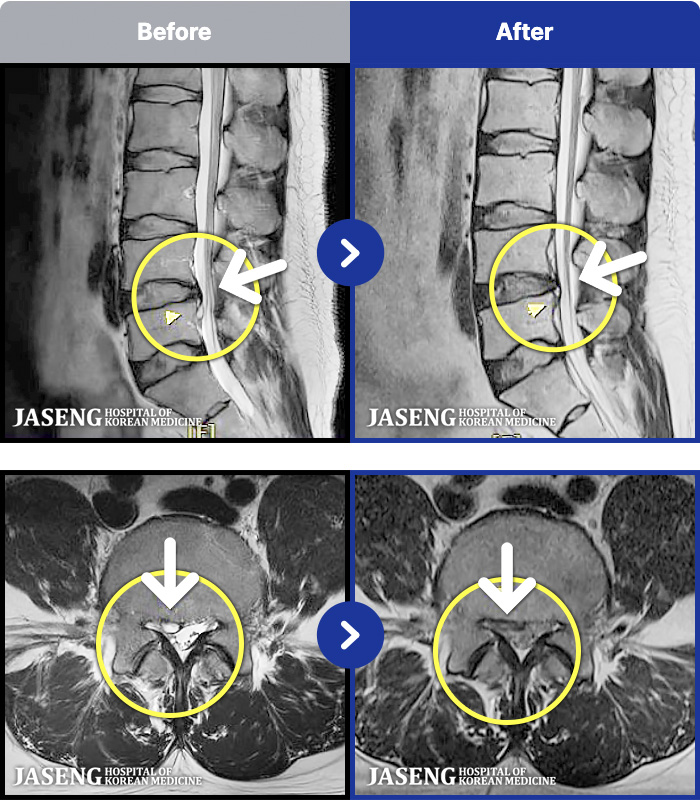

[뱸] 19.11.28~25.05.06